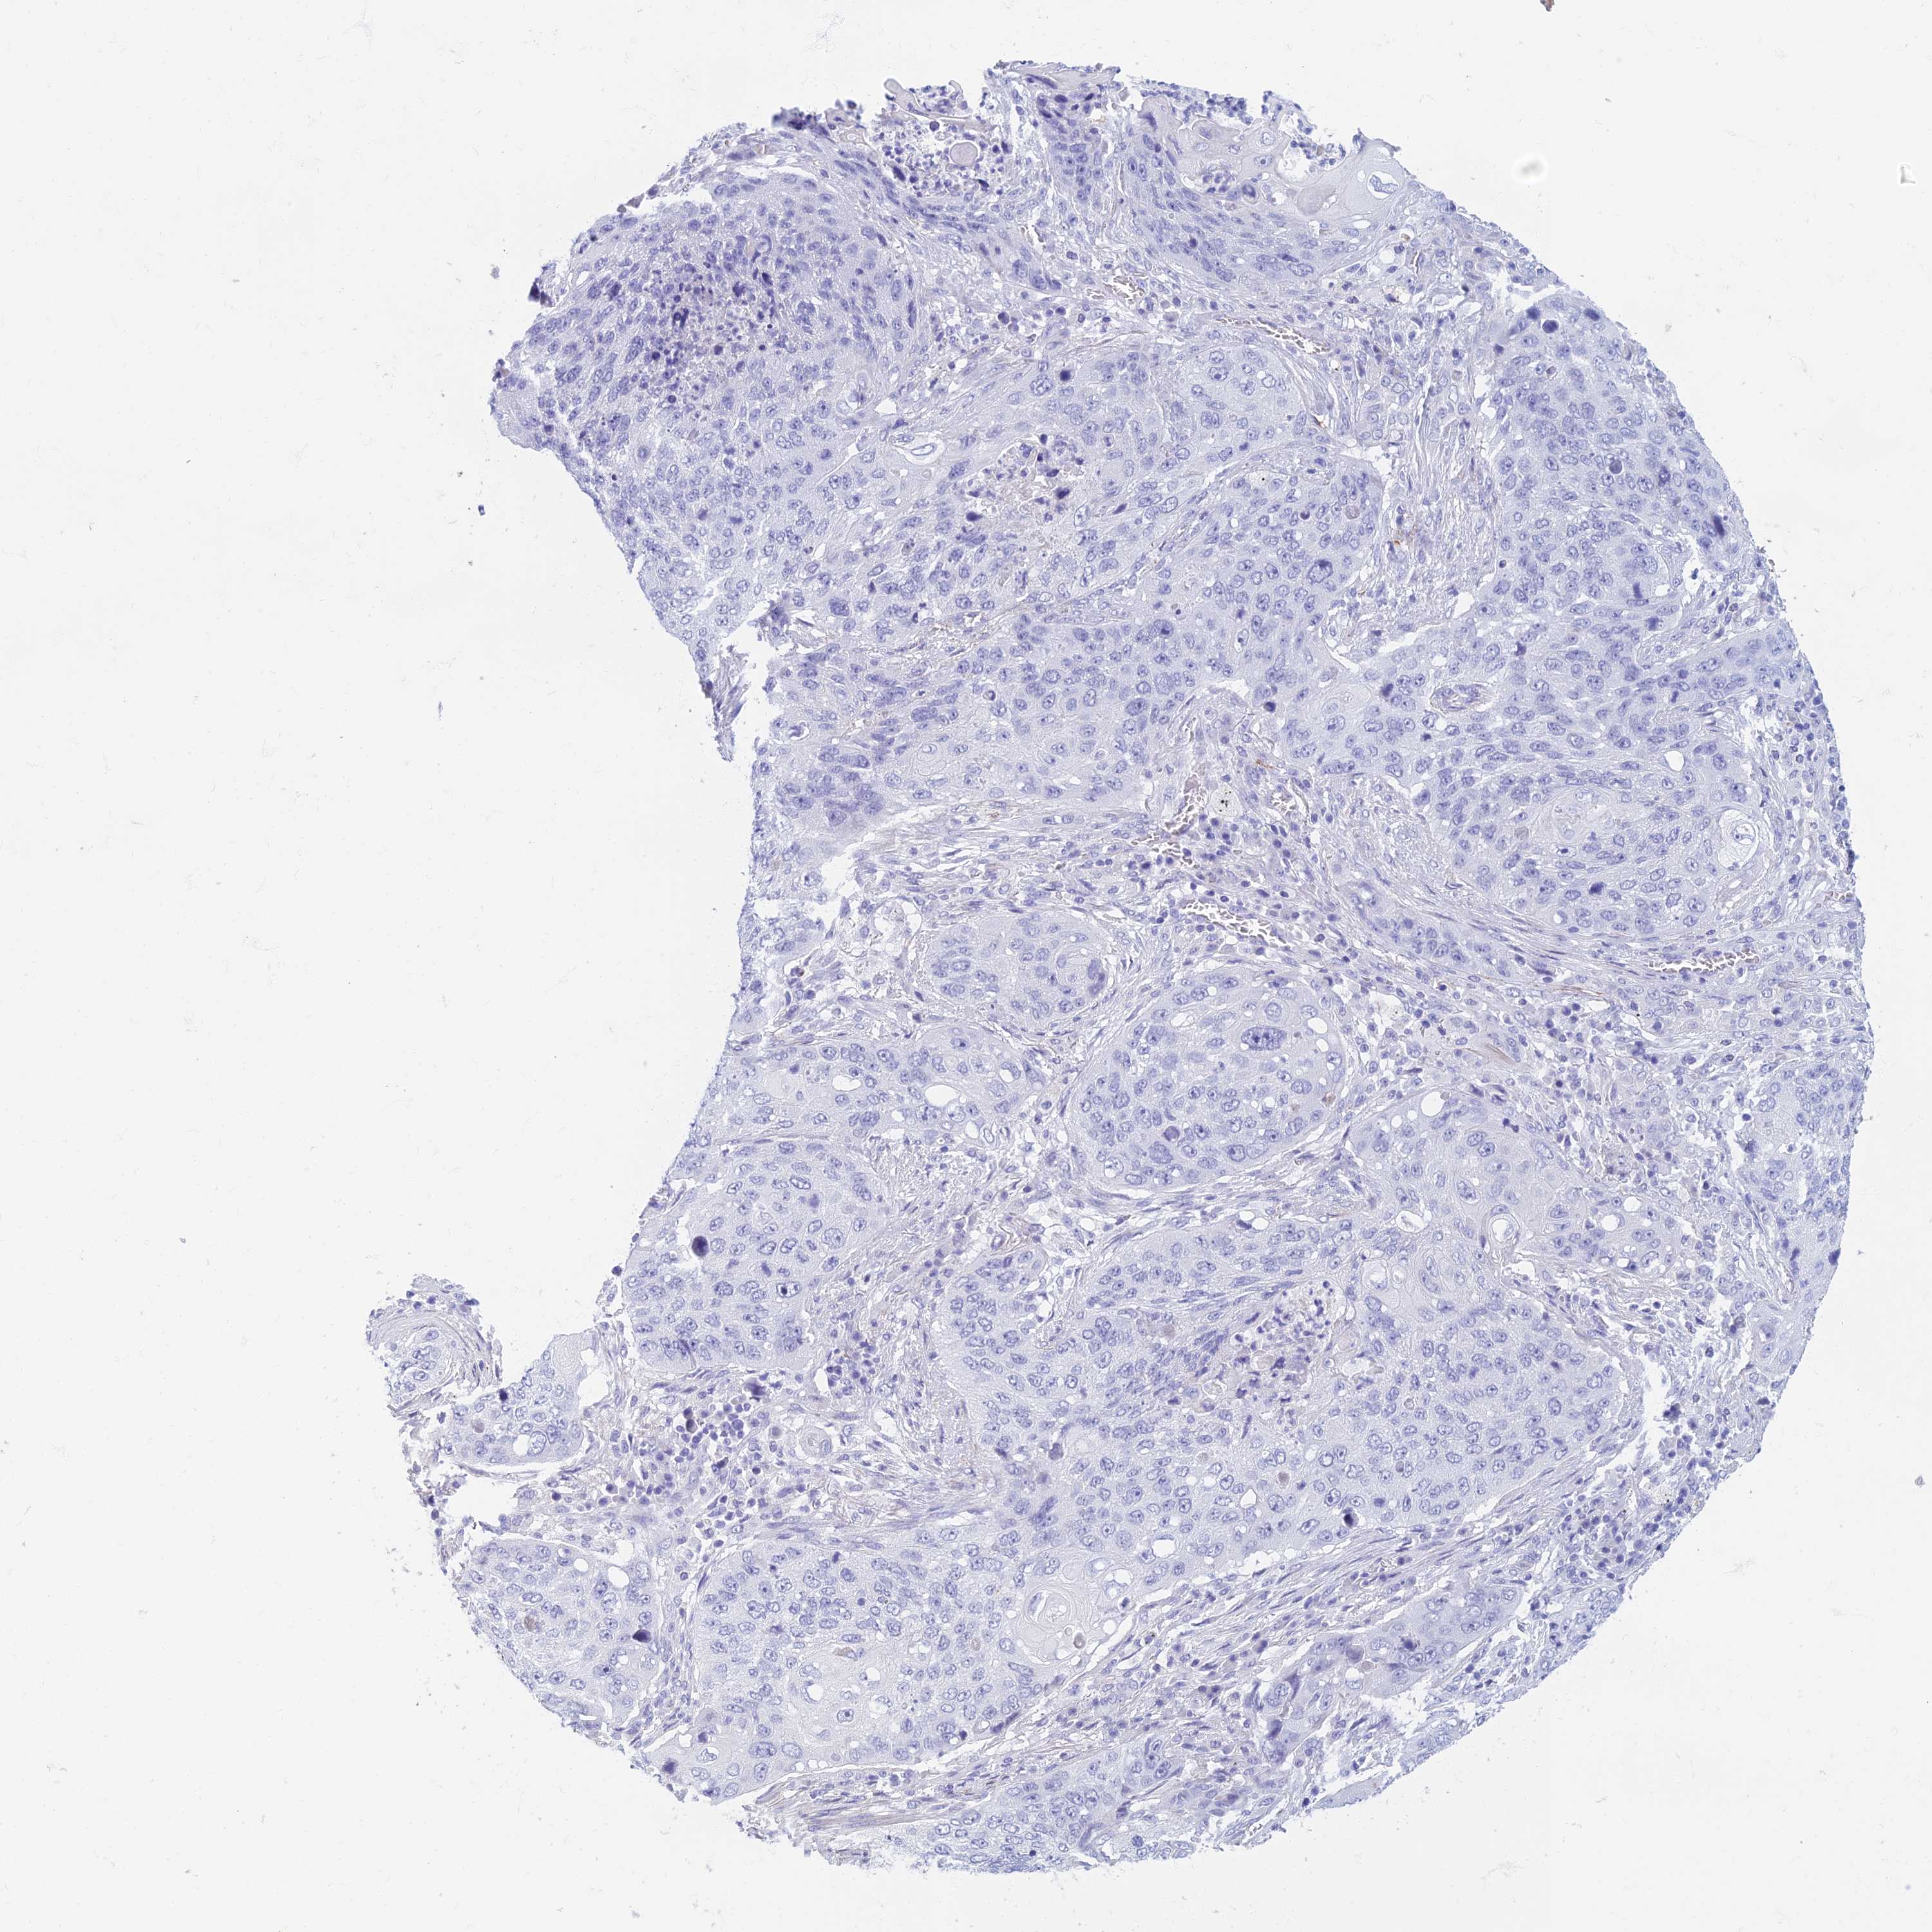

LUNG ADENOCARCINOMA (VALIDATION) - Interactive survival scatter ploti

The Survival Scatter plot shows the clinical status (i.e. dead or alive) for all individuals in the patient cohort, based on the same data that underlies the corresponding Kaplan-Meier plots. Patients that are alive at last time for follow-up are shown in blue and patients who have died during the study are shown in red.

The x-axis shows the expression levels (FPKM) of the investigated gene in the tumor tissue at the time of diagnosis. The y-axis shows the follow-up time after diagnosis (years). Both axes are complimented with kernel density curves demonstrating the data density over the axes. The top density plot shows the expression levels (FPKM) distribution among dead (red) and alive patients (blue). The right density plot shows the data density of the survived years of dead patients with high and low expression levels respectively, stratified using the cutoff indicated by the vertical dashed line through the Survival Scatter plot. This cutoff is automatically defined based on the FPKM cutoff that minimizes the p-score. The cutoff can be changed by dragging the vertical line or by entering a cutoff value in the square labeled "Current cut-off".

Under the Survival Scatter plot the p-score landscape (black curve; left axis) is shown together with dead median separation (red curve; right axis). Dead median separation is the difference in median mRNA expression between patients who have died with high and low expression, respectively. It is calculated as follows: median FPKM expression of dead patients with high expression - median FPKM expression of dead patients with low expression. This is intended to aid the user in visually exploring custom cutoffs and the associated p-scores and dead median separation.

Individual patient data is displayed and can be filtered by clicking on one or more of the category buttons on the top of the page. Categories describing expression level and patient information include: high, low, alive, dead, female, male and tumor stages. The scale of the x-axis can be toggled between linear and log-scale by clicking on the "x log" button. Mouse-over function shows TCGA ID, patient information and mRNA expression (FPKM) for each patient.

& Survival analysisi

Kaplan-Meier plots summarize results from analysis of correlation between mRNA expression level and patient survival. Patients were divided based on level of expression into one of the two groups "low" (under cut off) or "high" (over cut off). X-axis shows time for survival (years) and y-axis shows the probability of survival, where 1.0 corresponds to 100 percent.

ETFRF1 is not prognostic in Lung Adenocarcinoma (validation)

: 26.23

P scorei

N/A

Average pTPM 32.3

Number of samples 105